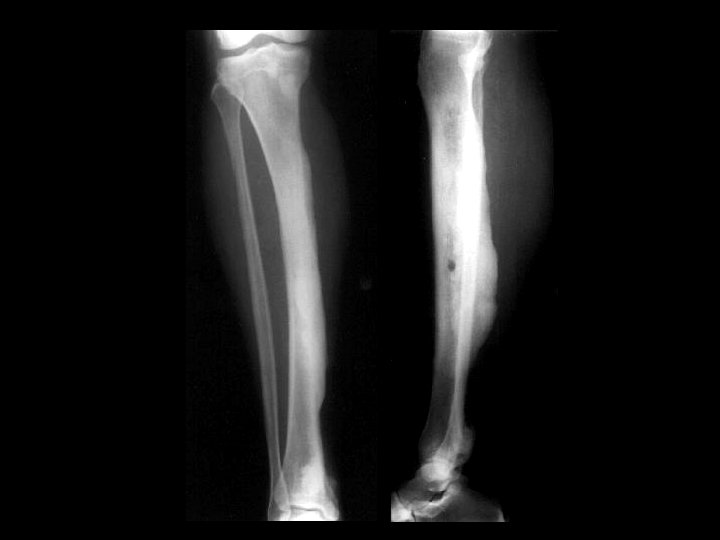

Melorheostosis • • • Findings: – Peripheral hyperostosis of the tibia producing a wavy sclerotic diaphyseal contour Rare bone disorder of childhood “candle wax” dripping down the bone appearance presents with PAIN and joint swelling ddx: – Paget’s – myelofibrosis – renal osteodystrophy – sclerotic mets